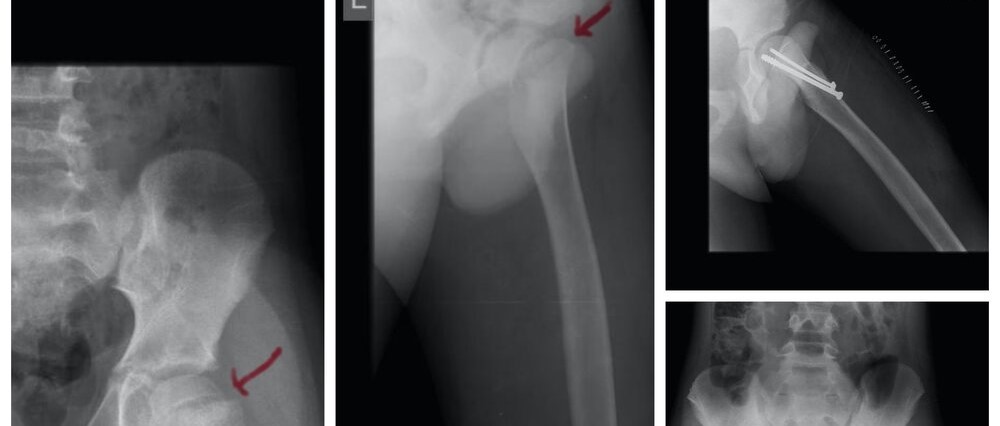

Traumatic Slip of Upper Femoral Epiphysis

Slip of the upper femoral epiphysis known as Slipped Capital Femoral Epiphysis (SCFE) develops during periods of rapid growth,..